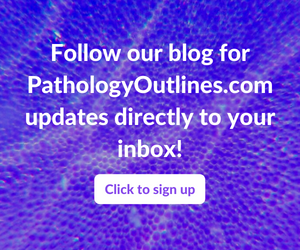

- Highly sensitive (98 - 100%) and specific (100%) nuclear marker for solitary fibrous tumor at all anatomical locations, regardless of tumor morphology (Pathology 2014;46:389, Mod Pathol 2014;27:390, Am J Surg Pathol 2014;38:552)

- NAB2::STAT6 fusion gene acts as activator of EGR1 (early growth response 1) targeted transcription and relocates to the nucleus, with resultant strong nuclear expression of STAT6 by immunohistochemistry (Mod Pathol 2014;27:390, Am J Clin Pathol 2015;143:672)

- Nuclear stain

Positive staining - normal

- Differences in background positive staining may be influenced by antibody clone used (Pathology 2014;46:389, Am J Clin Pathol 2015;143:672)

- Scar (24%, nuclear and cytoplasmic) (Am J Clin Pathol 2015;143:672)

- Adipose tissue (8%) (Am J Clin Pathol 2015;143:672)

- Solitary fibrous tumor (98 - 100%), regardless of morphology or site, typically strong and diffuse (Pathology 2014;46:389, Pediatr Dev Pathol 2018;21:389, Acta Neuropathol 2013;125:651)